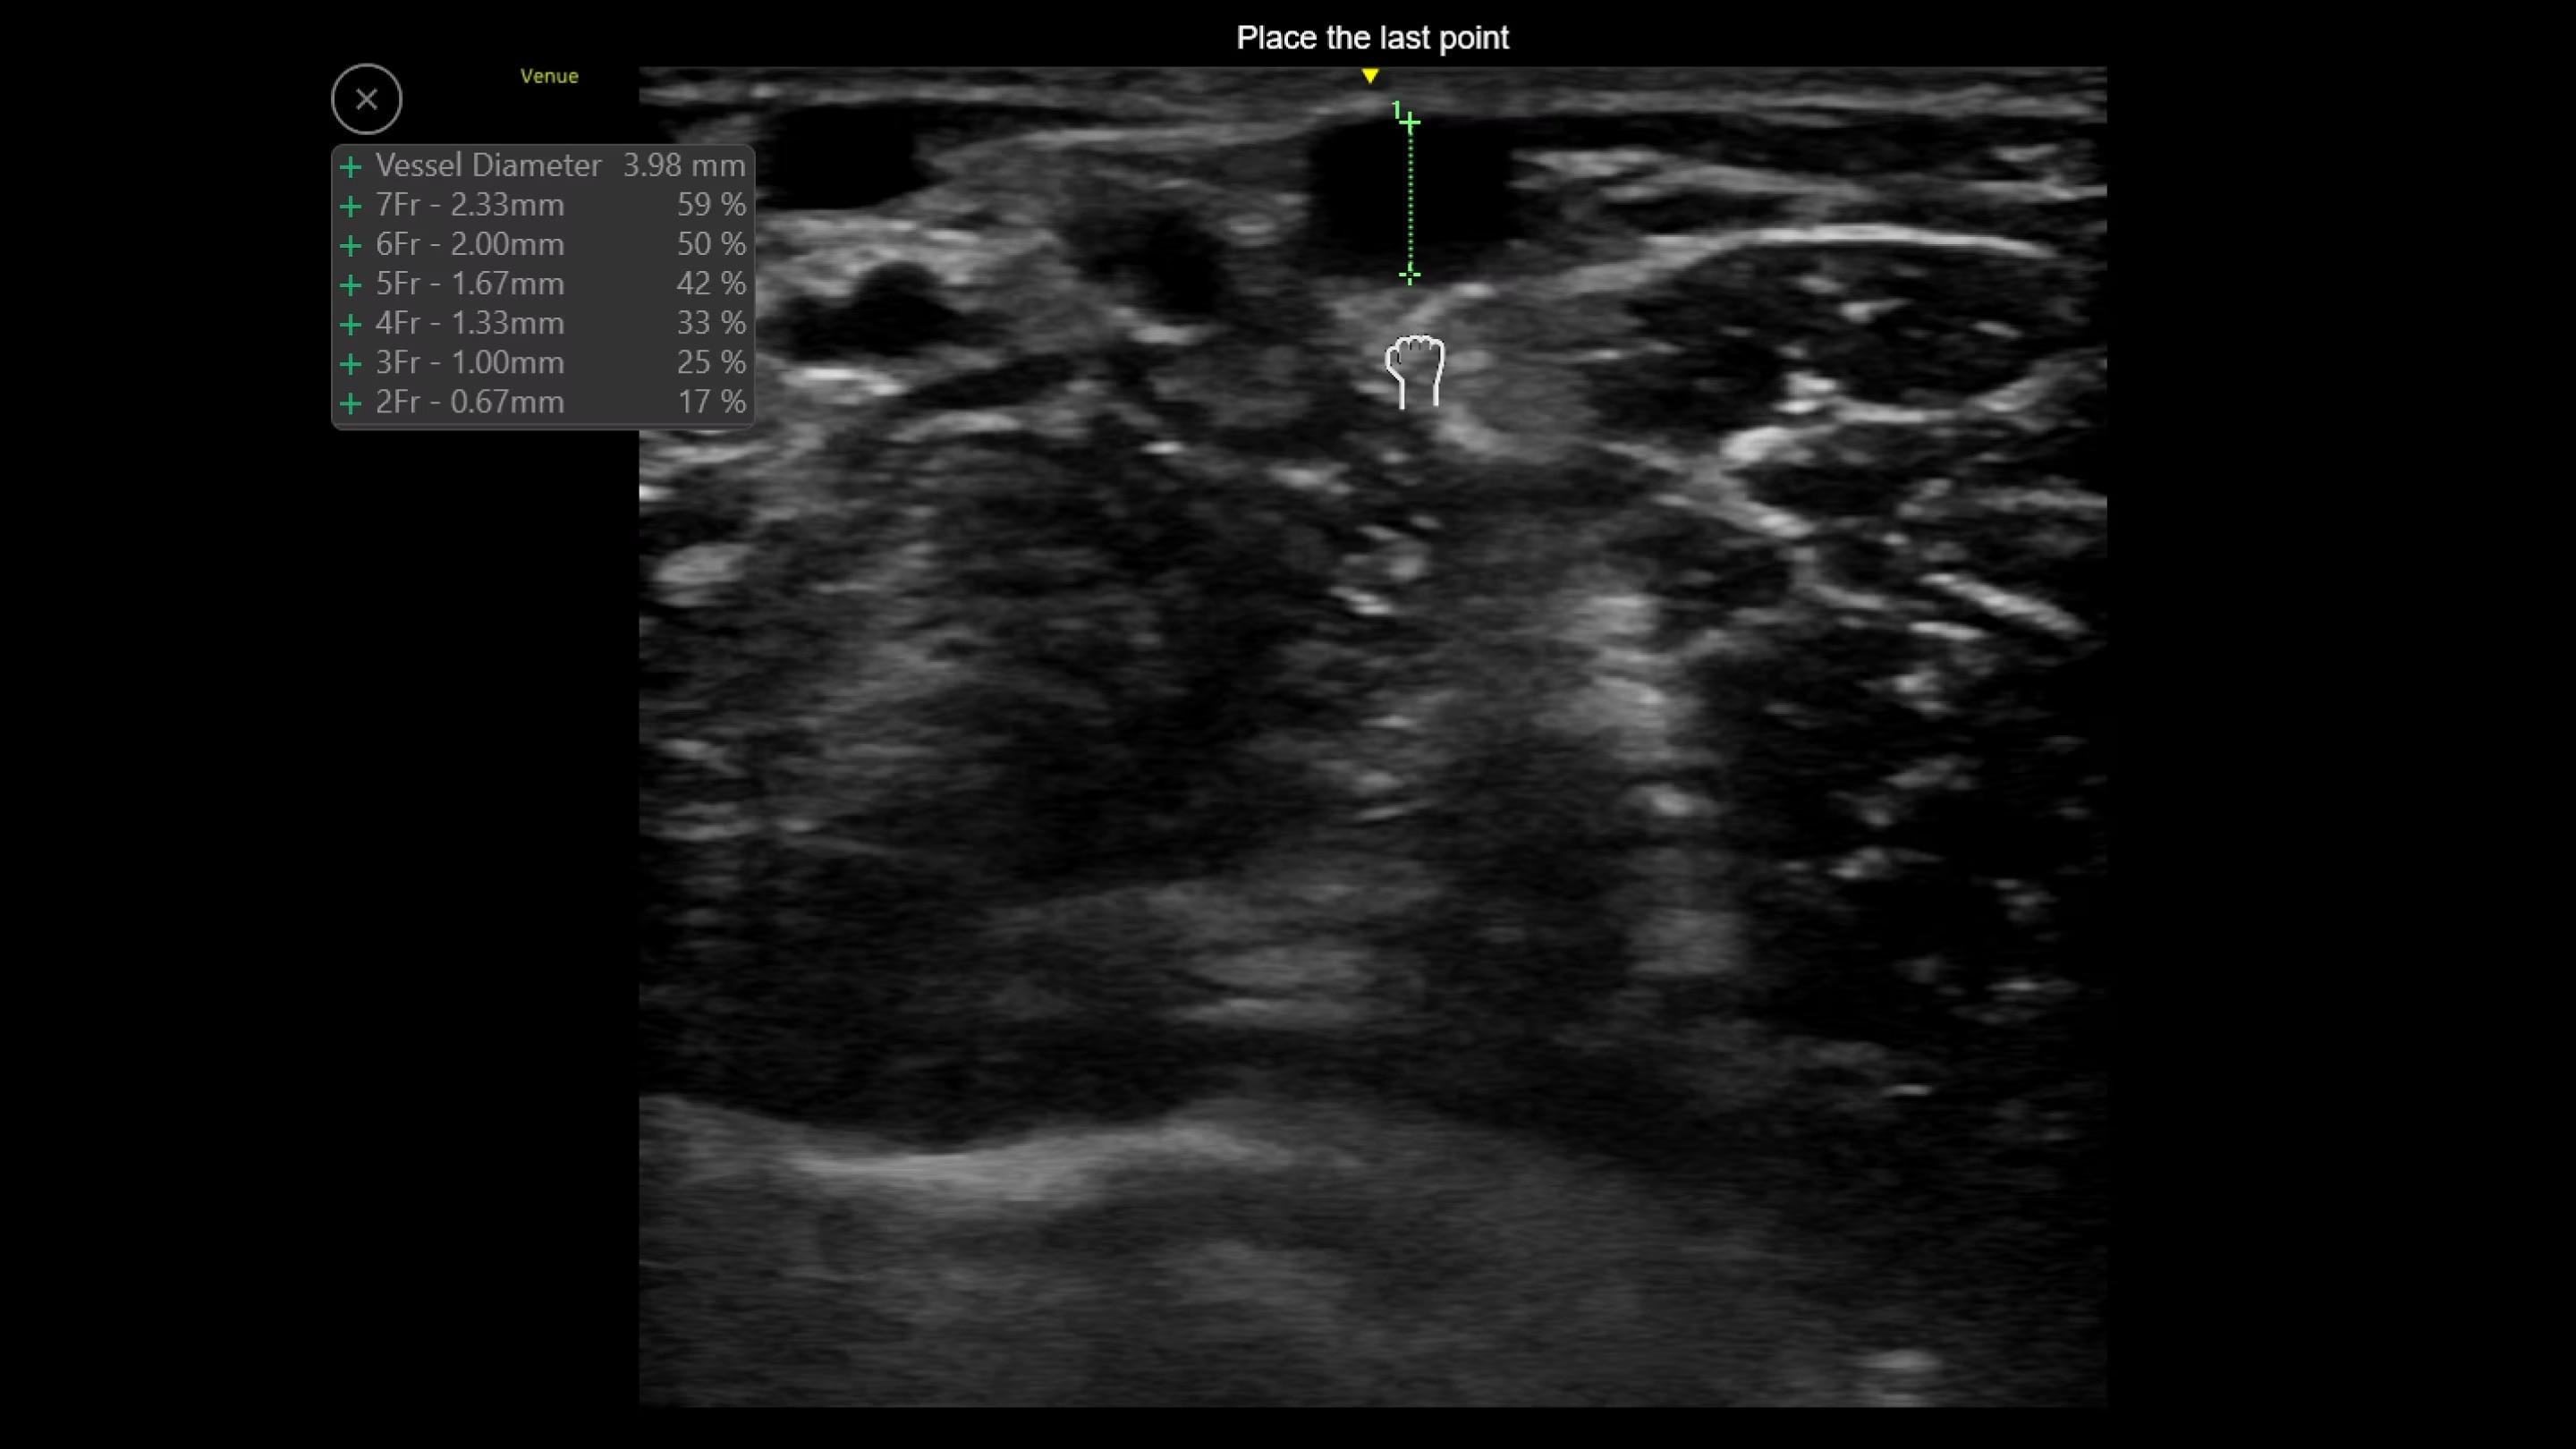

Shock Toolkit

Automated shock assessment

Medical shock in its many forms is a leading cause of death around the world.1 While ultrasound can help identify the cause of shock, it can require many manual steps and the guidelines can be complex. The Shock Toolkit quickly gets you the information you need to make fast decisions when triaging patients in shock. With tools such as Auto B-Lines, Auto VTI and Auto IVC, it simplifies a complicated process by utilizing automated calculations that focus on key indicators of patient status; the heart, lungs and inferior vena cava.